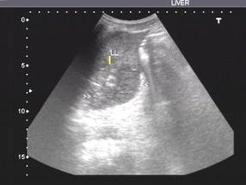

♥妊娠期肝血肿及破裂

自1844年Abercrombie报道首例与妊娠有关的肝破裂以来,共有100余例有关肝脏血肿及破裂的文献报道。该病来势凶险,预后差,死亡率高。临床产科医师的早期怀疑和及时诊断为有效的处理提供宝贵的时机。但是由于肝脏血肿及破裂的发病率很低,临床医师有关的知识和经验十分有限,给及时诊断带来了困难。因此加强妊娠期肝脏血肿的理解对降低孕产妇死亡率十分重要。